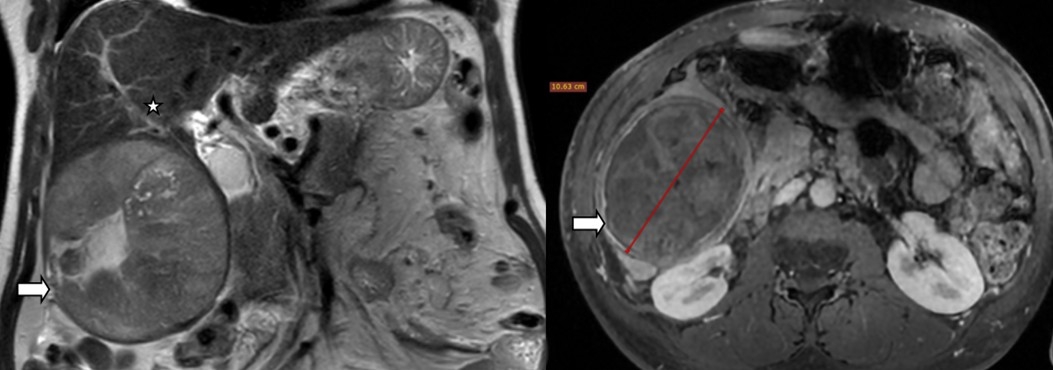

En RCP, le cas a été jugé non éligible à la chirurgie ou à la TACE. Le patient, après avoir refusé cette décision, a requis activement une TACE. Le geste a été réalisé par cathétérisme fémoral à l’aide d’une sonde Cobra 4F, d’un mélange de Lipiodol (10 ml), de Doxorubicine (50 mg) et de gélatine résorbable en purée. La procédure s’est déroulée sans incident. Le suivi à 6 mois a montré une bonne amélioration clinique l’amendement complet des signes. L’IRM de contrôle a objectivé un nodule inactif avec réduction significative de la taille, l’absence de signe de progression locale (Fig2).

Figure 2 : IRM à 6 mois en séquences coronale T2 SE (gauche) et axiale T2 FS (droite) Réduction majeure de la taille de la lésion (flèche) passant de 14 à 10 cm avec un pôle supérieur à distance de la branche portale droite (étoile).